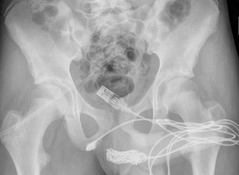

After an X-ray determined the exact position and size of the cable, surgeons cut lengthways into the boy’s bulbospongiosus muscle – an area between the genitals and the anus – and cut the knotted section of the cable.

Doctors had to cut open a muscle between the teen’s genitals and anus to cut the knot out of the cable